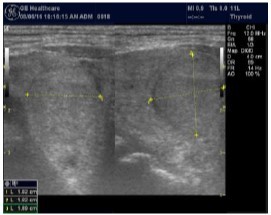

The reported prevalence of nodular thyroid disease depends on the population studied and the methods used to detect nodules 16. Our study population is unique as it is composed entirely of ESKD patients. We also used ultrasound as a method of detecting thyroid abnormalities. In our study the prevalence of thyroid nodular pathology as detected by ultrasound was found to be 57.6% mirror image what reported in the literature as it has been reported that nodules found on ultrasonography suggest a prevalence of 19 to 67%17, 18; and in other publications it has been reported to range from 50% to 70% 7, 8. Figure 3A below shows an Ultrasound detected thyroid nodule.

The prevalence of thyroid nodule is also influenced by age. In one study, 30 % of subjects 19 to 50 years of age had an incidental nodule on ultrasonography19. However, from our work we found that the presence of nodules increases with age. This may explain the reported low incidence of thyroid nodule in the age group 19-50 years. Also, with the widespread use of sensitive imaging in clinical practice, incidental thyroid nodules are being discovered with increasing frequency.

High-resolution ultrasonography (USG) is the most accurate and cost-effective method for evaluating and observing thyroid nodules 3. Although there is some overlap between ultrasound appearance of benign and malignant nodules, certain USG features are helpful in differentiating the two. Iso-or hyper-echogenicity of the thyroid nodule in conjunction with a spongiform appearance is the most reliable criterion for benignity of the nodule on gray-scale ultrasound, Figure 4A. Other features like nodule size <1 cm, width > length, presence of hypoechoic or hyperoechoic halo around the nodule, Figure 4A and Figure 4B, caused by fibrous capsule compressing thyroid tissue, and coarse/curvilinear calcification are less specific but may be useful ancillary signs4 ,6. "Ring down" or "comet-tail" artifact or sign is typical of benign cystic colloid nodule, Figure 520. Perinodular flow or spoke-and-wheel-like appearance of vessels on color Doppler examination is characteristic of a benign thyroid nodule. However, this flow pattern may also be seen in thyroid malignancy. A complete avascular nodule is very unlikely to be malignant 4.